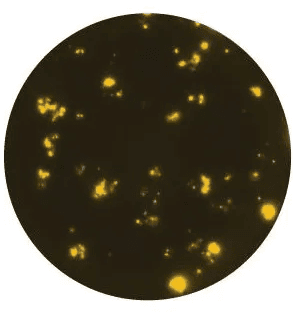

IgG-FluoroSpot using tetanus toxoid, biotin